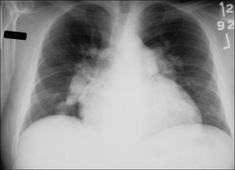

image

Figure 28.3 Chronic dyspnoea. Shadowing in the right lower zone. Apply Golden Rule 3—you only look for what you know. CXR conclusion—collapse of the right lower lobe.